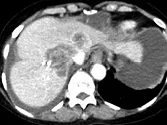

Figure 8. Carcinome hépatocellulaire. Sur l’examen initial (A, B), on observe

une lésion faiblement rehaussée au temps artériel (A), mais avec un lavage

évident au temps portal (B). Après six mois de chimiothérapie (C, D), la lésion est moins hypervascularisée au temps artériel (C), et de larges plages de nécrose sont apparues aux temps artériel et portal (D). La lésion est « PR » selon mRECIST